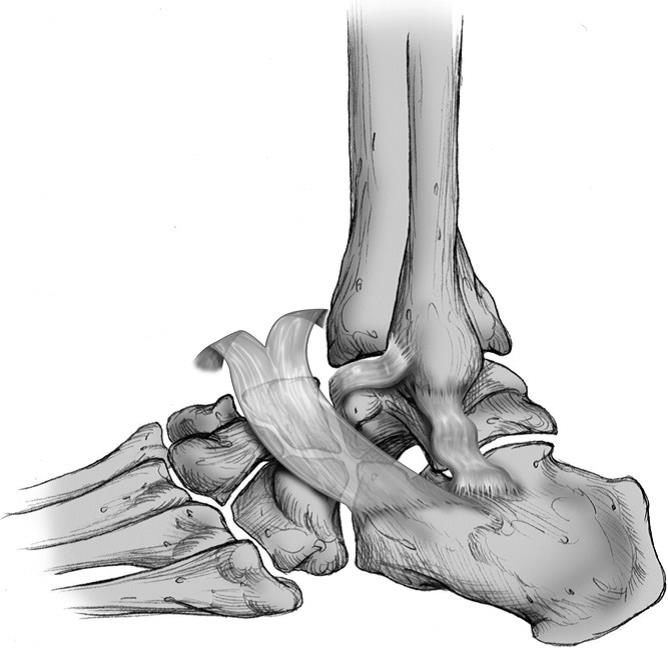

Анатомические фото голеностопного сустава и его суставных поверхностей